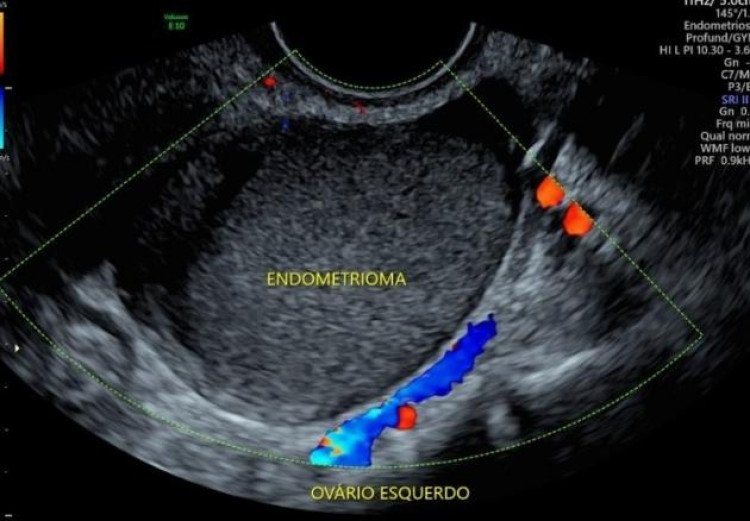

A endometriose é uma condição ginecológica inflamatória crônica que ocasiona o crescimento do tecido que reveste o útero fora da cavidade uterina. Nas mulheres com a doença, o tecido semelhante ao endométrio (que reveste o útero) cresce fora do útero em órgãos como ovários, intestino e bexiga, o que causa reações inflamatórias.